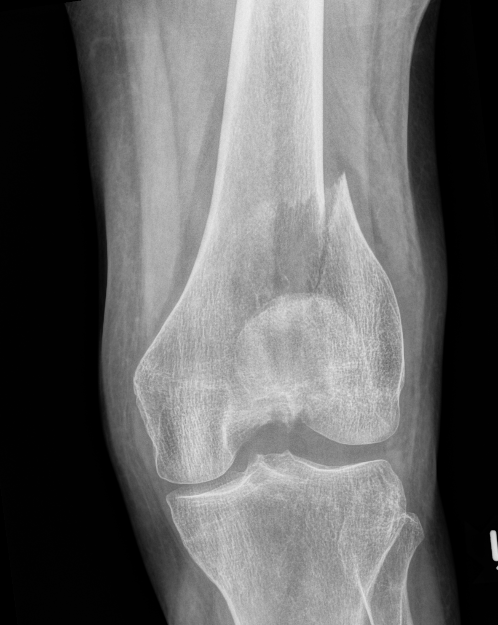

AO Type B1 & B2: Partial articular

![]()

Definition

Medial or lateral sagittal split

Technique

ORIF

- medial or lateral approach based on fracture location

- reduce articular split and fix with screws

- medial or lateral buttress plate

Lateral split fracture distal femur